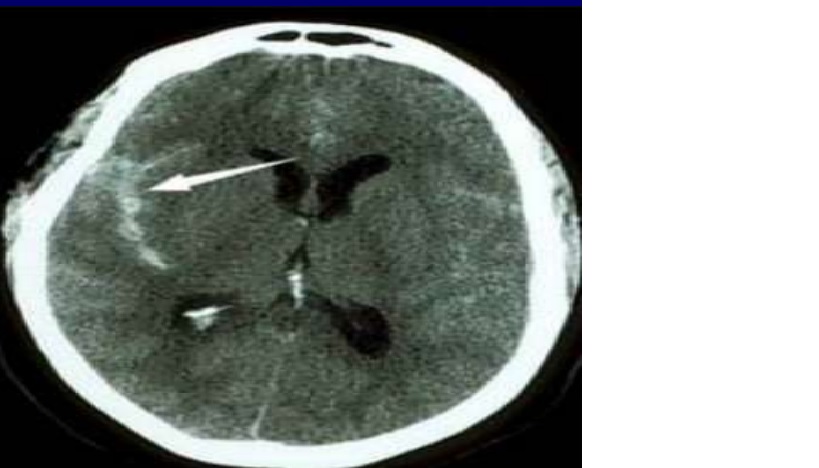

A noncontrast head CT revealed subarachnoid hemorrhage (SAH) in multiple cisterns, intraventricular hemorrhage, and mild hydrocephalus

Neuroimaging of the patient in CASE 1. Noncontrast head CT (A) showing acute subarachnoid hemorrhage, and two-dimensional (B) and three-dimensional (C) four-vessel angiogram showing a large top of the basilar artery aneurysm with an irregular shape (B, C, arrows). Two-dimensional angiogram after coiling shows obliteration of the aneurysm (D, arrow)

Nhận xét: Trường hợp này xử trí SAH giai đoạn đầu: chẩn đoán nhanh chóng SAH, hydrocephalus và điều trị cấp cứu ngay lập tức với hạ huyết áp, đặt EVD, và xóa bỏ túi phình động mạch não bị vỡ.